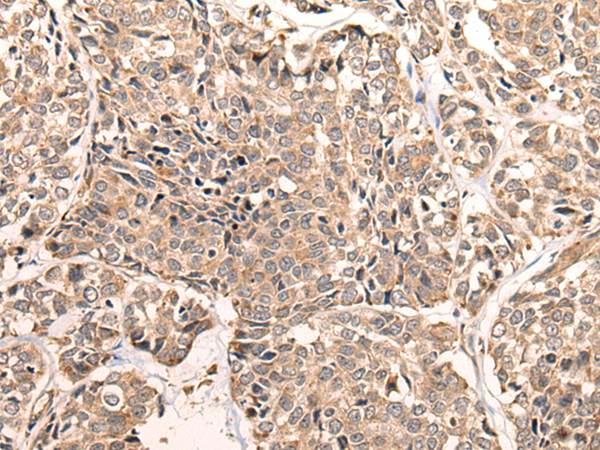

IHC positive control:

Human liver cancer and human esophagus cancer